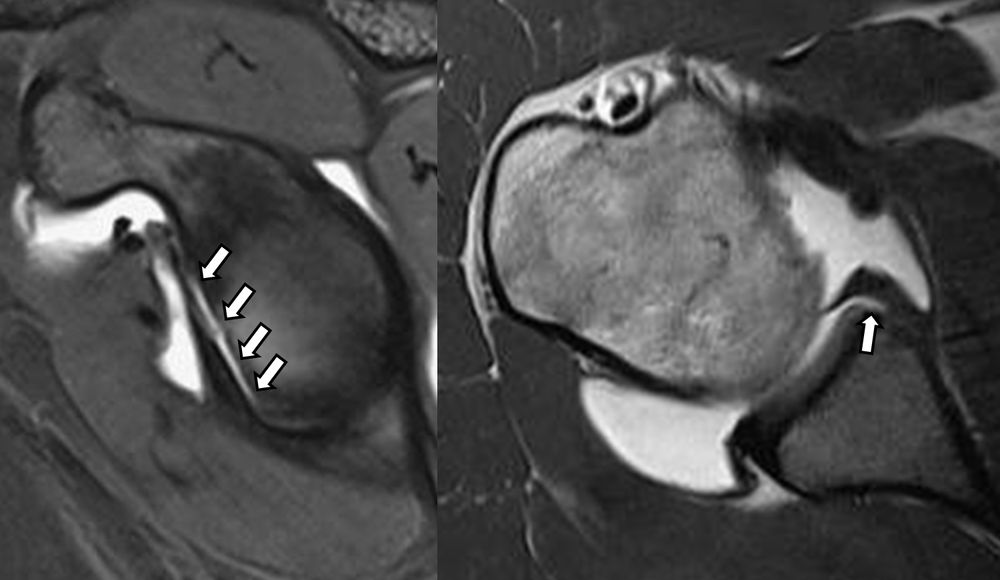

Είναι μια ελάχιστα επεμβατική απεικονιστική μέθοδος που επιτρέπει τη λεπτομερέστερη διερεύνηση του εσωτερικού των αρθρώσεων. Η ασφαλής έγχυση σκιαγραφικού εντός της άρθρωσης υπό ακτινολογική καθοδήγηση και η ακόλουθη απεικόνιση της άρθρωσης με αξονική ή μαγνητική τομογραφία (ή και με συνδυασμό των μεθόδων) αποσαφηνίζει βλάβες του χόνδρου και κακώσεις-ρήξεις συνδέσμων και τενόντων με υψηλή ακρίβεια, συμβάλλοντας σημαντικά στο λεπτομερή χειρουργικό σχεδιασμό.